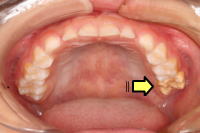

MIH(6才臼歯と前歯の形成不全)

6才臼歯と前歯に限られる異常で、白濁や褐色の変色や、穴が空いたりしています。虫歯ではありませんが、崩れやすいために、定期診査を受けましょう。

写真の左右の6才臼歯の色が違い、

左上と右下の6才臼歯がMIHです。

日本では19.8%の子に見られ、九州や四国など西日本の方が多いようです。

(7〜9才、日本小児歯科学会2018)